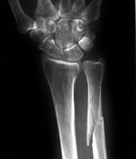

Trauma Radiography

Additionally, the emergency room (ER) is a typical site for portable radiography and even fluoroscopy. Trauma radiographers provide the images that are often required to make the initial diagnosis that determines the patients course of treatment. Whether an injury is caused by a traffic accident, a fall, a gun-shot wound, or an explosion -- the first golden hour is extremely important to the success of recovery.

Trauma radiography done in the emergency room using portable equipment, or in the imaging department, requires working quickly and accurately in stressful situations.